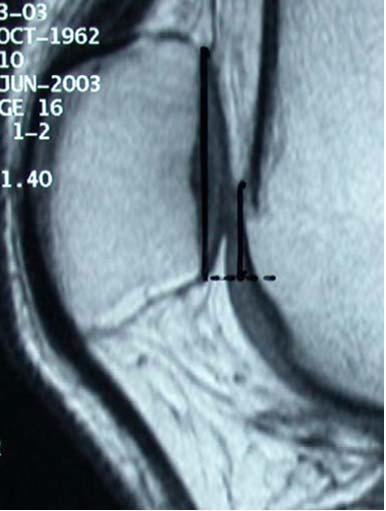

MPFL footprint. Ved gennemlysning og anatomisk

Insall-Salvati ratio ved måling af

patella højde index: Patella sene længde

/patella højde